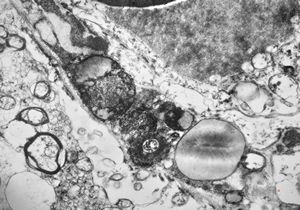

M,71y. | CADASIL accompanied with Alzheimer disease - brain vessel - arrows: granular osmiophilic material (GOM) between basement membranes

M,71y. | CADASIL accompanied with Alzheimer disease - brain vessel - arrows: granular osmiophilic material (GOM) between basement membranes

M,71y. | CADASIL accompanied with Alzheimer disease - brain vessel - arrow: granular osmiophilic material (GOM) in basement membrane